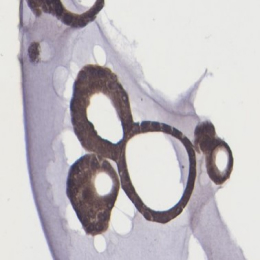

Pancreatic cancer organoid

H&E | ANXA1 | ANXA10 | ANXA13 | |

|---|---|---|---|---|

Cancer tissue | ![]() | ![]() | ![]() | ![]() |

Cancer organoid | ![]() | ![]() | ![]() | ![]() |